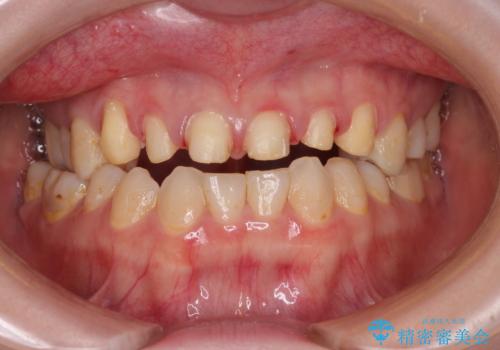

- 前歯の色味が気になるとのことで来院された患者様です。今までに保険のプラスチック(コンポジットレジン)で虫歯の治療をしており経年的な劣化により着色が目立つようになっていました。また歯と歯の隣り合っているところに段差もあり虫歯になっているところもあったため前歯6本のオールセラミッククラウンによる治療を行うこととなりました。